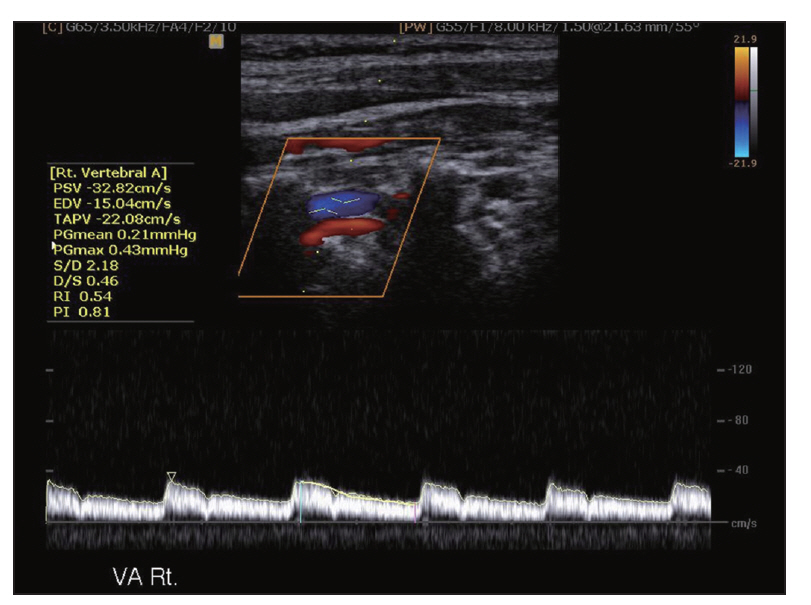

Carotid Doppler ultrasonography is a popular tool for evaluating atherosclerosis of the carotid artery. Its two-dimensional gray scale can be used for measuring the intima-media thickness, which is very good biomarker for atherosclerosis and can aid in plaque characterization. The plaque morphology is related to the risk of stroke. The ulceration of plaque is also known as one of the strong predictors of future embolic event risk. Color Doppler ultrasonography and pulse Doppler ultrasonography have been used for detecting carotid artery stenosis. Doppler ultrasonography has unique physical properties. The operator should be familiar with the physics and other parameters of Doppler ultrasonography to perform optimal Doppler ultrasonography studies.